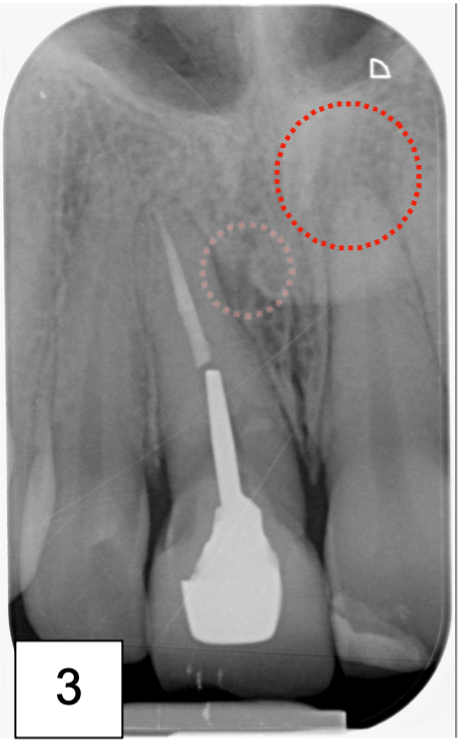

• Bilan rétro alvéolaire (Photo 3)

La radiographie rétro alvéolaire, met bien en évidence la présence d’une lésion au niveau du tiers médian radiculaire de cette 11.

Au niveau de 21, une lésion apicale est présente et un test au froid négatif confirme la nécrose de la dent et la nécessité de la réalisation d’un traitement endodontique.